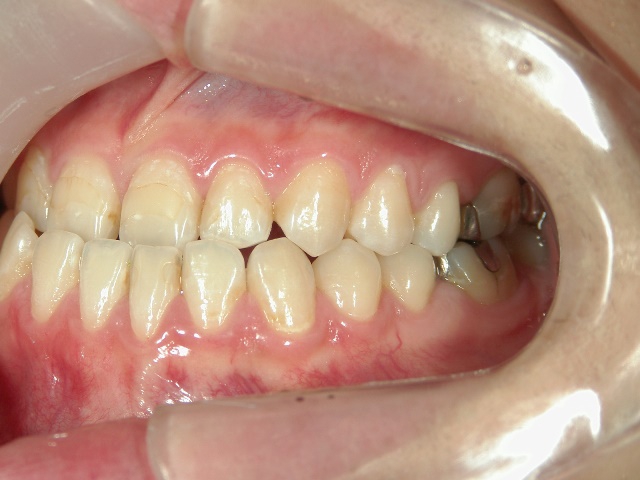

矯正歯科 治療前 急速拡大装置で上顎を広げた後、ワイヤーへ移行 非抜歯

no.31_7964_治療前_右 .JPGno.31_7964_治療前_正面 .JPGno.31_7964_治療前_左 .JPG